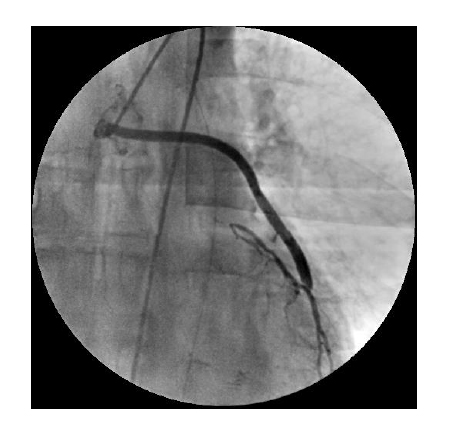

Thanks to an effective cooling system of the X-ray tube assembly, the system provides for a long period of X-ray control, which determines the use of the system for a wide range of diagnostic and medical-surgical manipulations on the heart and vessels. The subtraction angiography mode, the vascular package, the routing, and mask selection option create the necessary conditions for successful use of the system in coronary angiography, angiography, and control of electrophysiology procedures.